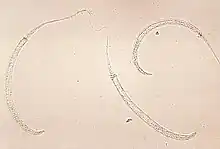

Dracunculus medinensis (Guinea worm, fiery serpent) is a nematode that causes dracunculiasis, also known as guinea worm disease.[1] The disease is caused by the female[2] which, at around 80 centimetres (31 inches) in length,[3] is among the longest nematodes infecting humans.[4] In contrast, the longest recorded male Guinea worm is only 4 cm (1+1⁄2 in).[3]

D. medinensis L1 larvae are found in fresh water, where they are ingested by copepods (small crustaceans) of the genus Cyclops. Within the copepod, the D. medinensis larvae develop to an infective L3 stage within 14 days.[5] When the infected copepod is ingested by a mammalian host drinking unfiltered water, the copepod is then dissolved by stomach acid and dies and the D. medinensis larvae are released and migrate through the wall of the mammalian intestine, and enter the abdominal cavity and retro-peritoneal space, where they mature into adults. After maturing and mating within the host, the males die and females (length 70–120 cm) migrate in subcutaneous tissue towards the skin's surface. Around a year after the infection, the female causes the formation of a blister on the skin's surface, generally on the lower extremities, though occasionally on the hand or scrotum. When the blister ruptures, the female slowly emerges over the course of several days or weeks.[5] This causes extreme pain and irritation to the host. During those few days to hours before the worm exits the skin, the person may develop a fever, pain, or swelling in that area. When the host — in an attempt to alleviate the excruciating burning pain — submerges the affected body part in water, the female releases thousands of larvae into the water. From here, the larvae infect copepods, continuing the life cycle.[5] After the worm exits the skin the wound caused by the emerging worm often develops a secondary bacterial infection. Permanent damage can occur if the infection goes untreated around a joint. Most cases occur in areas without access to health care facilities.[6]